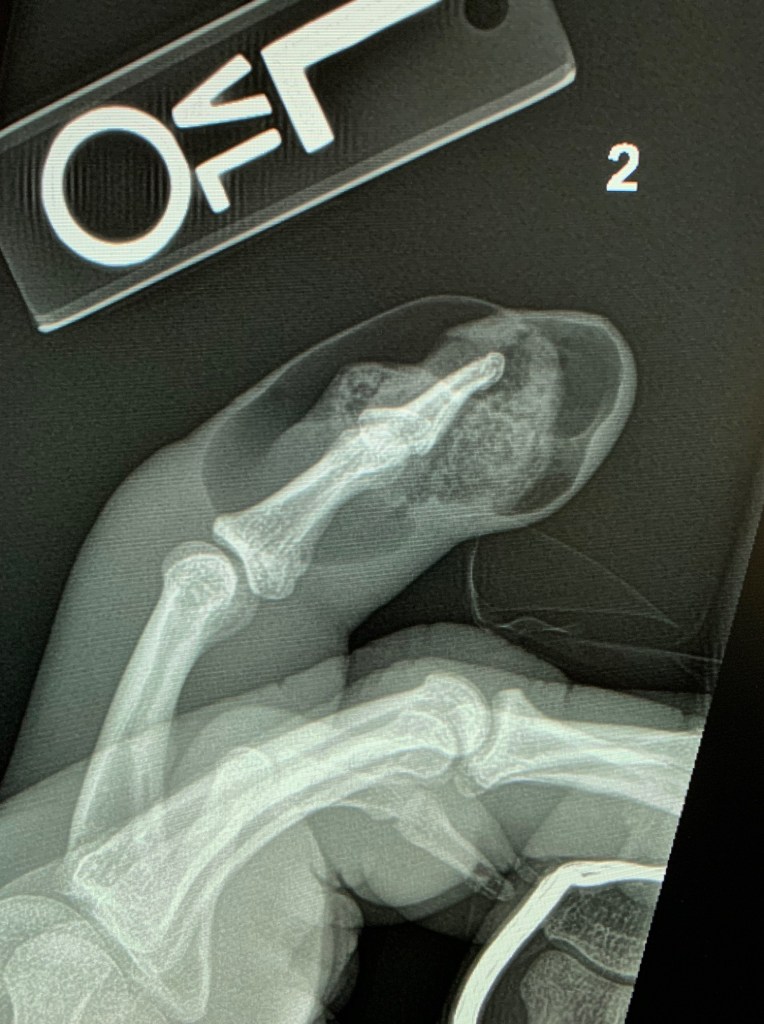

Radiograph of index finger shows soft tissue swelling and gas in the setting of infection.